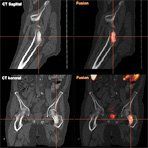

Osteoplastic Metastasis of Prostate Cancer in Choline PET/CT

In prostate cancer patients, an “unprecedented bone scan improvement” was observed. Based upon these results, Exelixis, the company that is developing cabozantinib will expand the prostate and ovarian cancer cohorts for this trial and also plans to initiate the first pivotal trial in prostate cancer by the end of this year.